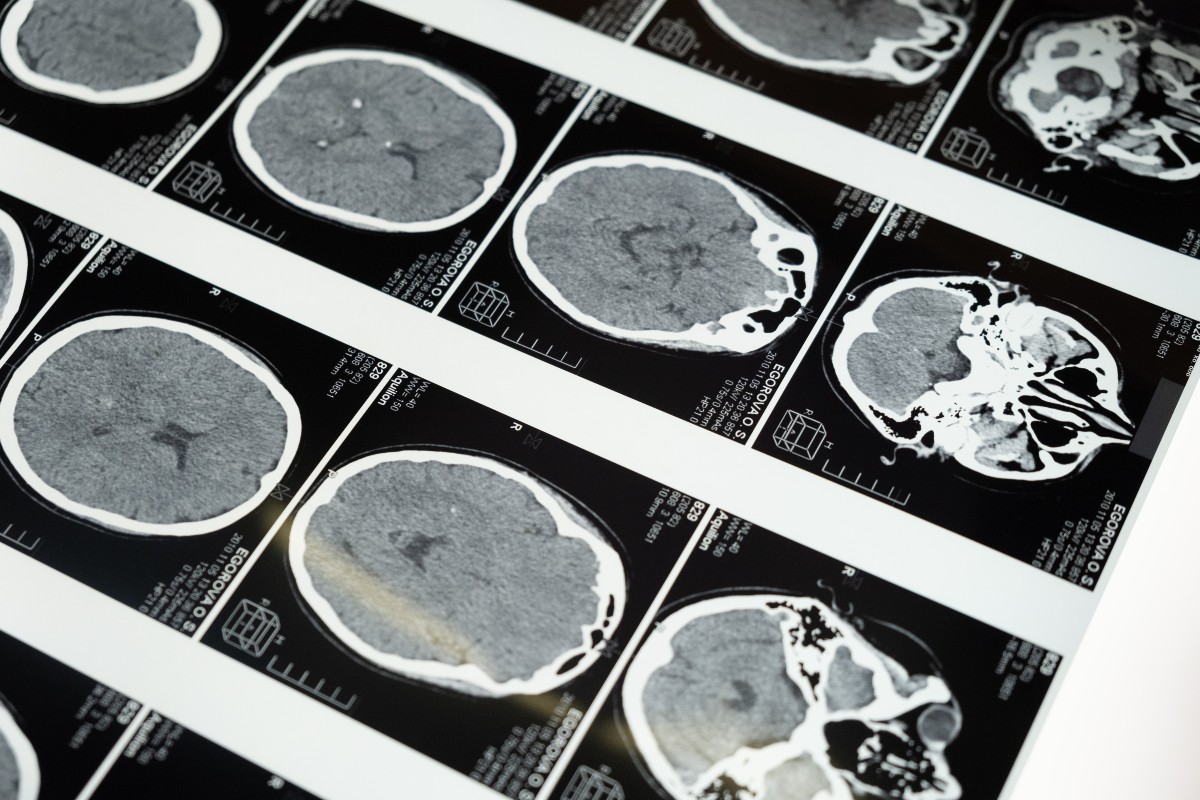

H επιστήμη πίσω απο το να διαβάζεις την σκέψη

Μια νύχτα του Οκτωβρίου του 2009, ένας άνδρας βρίσκεται μέσα στον Μαγνητικό Τομογράφο (MRI), στην Λιέγη του Βελγίου. Πριν από πέντε χρόνια κι έπειτα από ατύχημα με μοτοσυκλέτα, έπαθε κρανιοεγκεφαλική κάκωση και από τότε αδυνατεί να μιλήσει, βρισκόμενος στην λεγόμενη “κατάσταση φυτού”. Ένας νευροεπιστήμονας, με το όνομα Μάρτιν Μόντι, βρισκόταν στο διπλανό δωμάτιο μαζί με […]